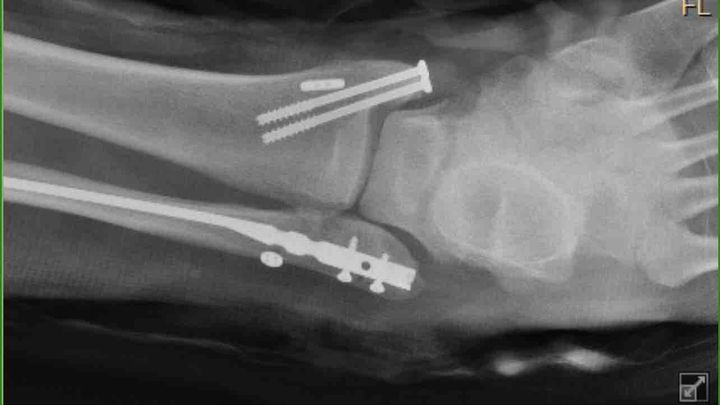

Hello, Matthew is the most kind person you will ever meet has the biggest heart.He loves the game and was born to play it, he literally eats, sleeps and breathes hockey. Matt is one to never ask for help, he is the one who is always helping others and go in the extra mile, he definitely is not used to sitting on the couch, being waiting on hand and foot. So this time around it’s the opposite. We are asking for help because even though we have insurance he is going to be out of work for a long time on the road to recovery, so we are asking for donations to help offset the cost of medical bills to come. Matthew maybe a quite person and not talk much, but you give him hockey skates and ice and he turns into a little kid in a candy store.Today while participating in a tournament in Pittsburgh he took a fall and found out that his ankle is broken in three different places and he is going to need two-three surgeries, we don’t know how long he is going to be out of work, recovery time and medical bills. I am seeking help from family, friends etc to help us with these huge expenses we are going to endure in the next months to come. I graciously appreciate everyone who can help, no amount is to small Thank you all in advance and we love you